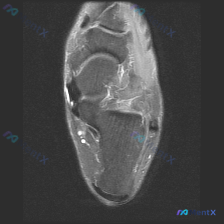

本次提供的是踝关节水平MRI T2序列轴位图像,影像观察结果如下:

- 骨骼结构:胫骨远端、腓骨远端、距骨穹窿骨皮质轮廓完整,无明显骨折线或显著骨髓信号异常

- 踝关节间隙:可见少量液性信号,提示存在少量关节积液

- 软组织与肌腱:

- 踝关节周围多组肌腱走行可见

- 核心异常发现:内踝后方及下方(胫骨后肌腱、趾长屈肌腱走行区)可见明显不规则团块状/条索状异常T2高信号,周围软组织弥漫性信号增高,提示液体积聚合并炎性水肿

- 外侧腓骨长短肌腱区域也可见少量液体围绕

- 本次单层面观察其他韧带信号尚可,无明确断裂回缩征象